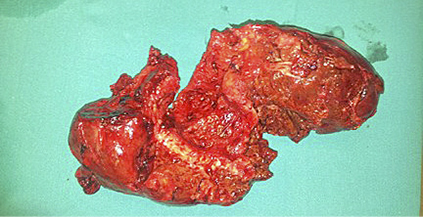

A 53 year old male patient presented with severe abdominal pain. The patient had been operated 3 times for liver hydatid cyst due to Echinococcus granulosus. The ultrasonography demonstrated no portal blood flow and portal vein thrombosis was detected. There were vesicular cystic lesions inside the portal vein. Dynamic computerized tomography of the liver revealed lesions initiating from periportal region and extending to both liver lobes, which were associated with the hydatid cyst (Figure 1).

Moreover, the thrombus of echinococcus was extending until the lumen of superior mesenteric vein.

There were numerous hydatid cysts in the liver. There were a lot of portal collaterals in the portal hilus because of the hydatid thrombus inside the portal vein. Right and mid hepatic veins could not be visualized due to the thrombosis.

Figure 1. CT scan